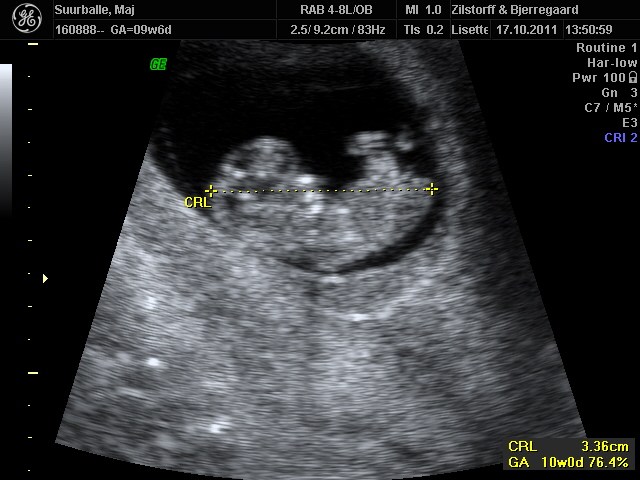

Ja, 10+0 sagde jordemoderen

Troede ikke at den var så "levende" allerede.. Den lille fister på knap 3,4 cm sprællede helt vildt jo! Og tænk at den allerede har arme, ben, små øre, noget der ligner øjne, næse...... HELT vildt at opleve <3